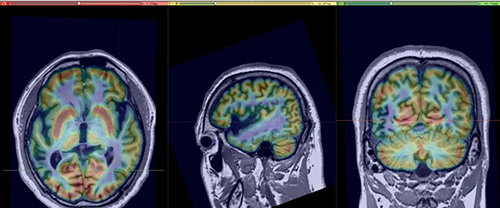

先进的影像融合技术

该患者为中年男性,37岁。饱受癫痫发作的痛苦30余年,4种抗癫痫药物治疗效果欠佳。2019年8月入住我院神经内科癫痫病区。在庞在英教授和冯亚波教授的指导下,林幽町博士带领团队成员韩玉香博士、杨丽玲博士和刘晓云博士等医护人员对患者进行了全面评估,经颅脑MRI及PET确定在右侧颞顶叶有一个明显伴有PET低代谢的软化灶。但是患者目前发作形式多样,认为可疑存在2个以上致痫灶,并且病灶靠近视觉皮层,如果评估不详细可能造成致痫灶切除不完全,导致患者术后仍会发作,如果手术涉及视觉功能区可能会造成视野及视觉受损。为了能够完全切除致痫灶并同时保护视觉功能区,在神经外科许尚臣教授联合会诊下决定行颅内深部电极植入并脑深部电极脑电图监测以进一步明确手术范围。

脑深部电极电生理监测可见病灶及周边区域大量癫痫样放电